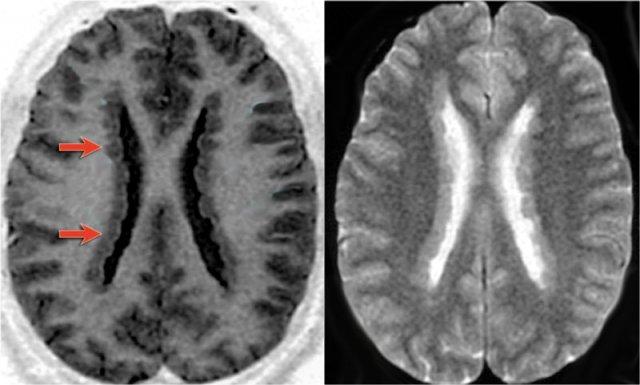

Ảnh chuỗi xung T1W, T2W và FLAIR mặt phẳng axial của bệnh nhân nam 15 tuổi bị động kinh.

Lưu ý hình ảnh dày và tăng tín hiệu vỏ não hồi trán trên bên trái.

Ảnh FLAIR cũng cho thấy tăng tín hiệu ở chất trắng dưới vỏ.

Các dấu hiệu này điển hình cho loạn sản vỏ não khu trú.

Dấu hiệu xuyên vỏ (Transmantle sign)

Đôi khi vùng tăng tín hiệu được thấy kéo dài từ vùng dưới vỏ đến bờ não thất.

Đây được gọi là dấu hiệu xuyên vỏ (transmantle sign).

Dấu hiệu này phản ánh tình trạng di cư tế bào thần kinh bị gián đoạn.

Hình ảnh của bệnh nhân nam 27 tuổi bị động kinh thùy chẩm kháng trị.

Ảnh FLAIR mặt phẳng coronal và T2W mặt phẳng axial cho thấy dày vỏ não tăng tín hiệu T2 và tăng tín hiệu ở vỏ não và vùng dưới vỏ.

Lưu ý vùng tăng tín hiệu dưới vỏ kéo dài đến não thất bên phải, biểu hiện dấu hiệu xuyên vỏ (mũi tên xanh).

Dấu hiệu xuyên vỏ (transmantle sign) ghi nhận ở một bệnh nhân khác bị loạn sản vỏ não khu trú.